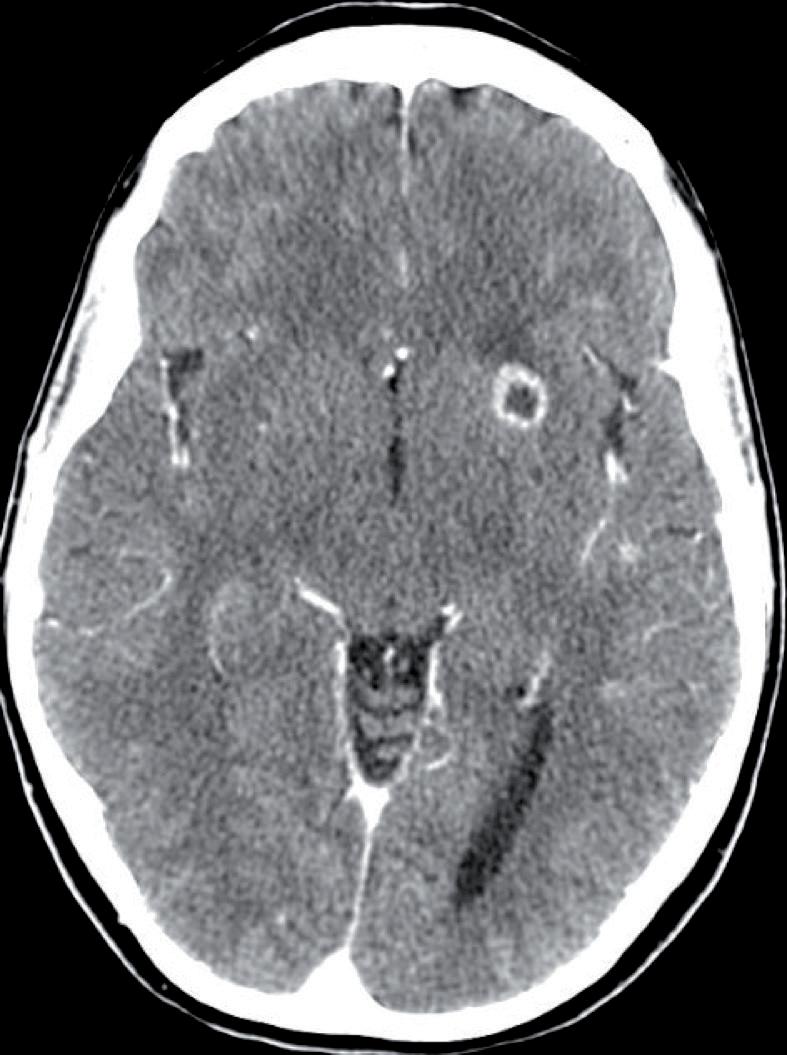

ziente accedeva in Pronto Soccorso, ove una risonanza magnetica dell’encefalo riscontrava multiple lesioni secondarie cerebrali. La paziente veniva quindi sottoposta a radioterapia panencefalica. Si avviava trattamento eziologico sistemico con trastuzumabemtansine (TDM-1), proseguito da Novembre 2020 per 28 mesi, ottenendo stabilità di malattia e buona tolleranza (episodica piastrinopenia G1). A Maggio 2024 la paziente lamentava ricomparsa di instabilità della marcia ed ipostenia degli arti superiori e inferiori, evolutisi nell’arco di 72 ore in completa impossibilità alla deambulazione, alla quale si associavano incontinenza urinaria e fecale. Recatasi in Pronto Soccorso, la

paziente veniva sottoposta a tomografia assiale computerizzata (TC) dell’encefalo, non dimostrativa, e a RM encefalo e rachide, la quale deponeva per disseminazione liquorale olo-cordica di neoplasia nota in anamnesi e multiple localizzazioni intraventricolari. Previa discussione multidisciplinare, si avviava trattamento di seconda linea con trastuzumab deruxtecan 5,4 mg/kg endovena ogni 21 giorni. La prima rivalutazione radiologica (20/08/2024) ha evidenziato la pressoché completa regressione delle lesioni ripetitive intra-midollari ed intraventricolari precedentemente descritte (figure 1 e 2). Permanevano riconoscibili unicamente due piccole lesioni focali all’altezza del passaggio T2-T3 e del passaggio T7-8, entrambe in riduzione dimensionale. Attualmente la paziente sta proseguendo il trattamento, con beneficio clinico ed iniziale ripresa della mobilità.